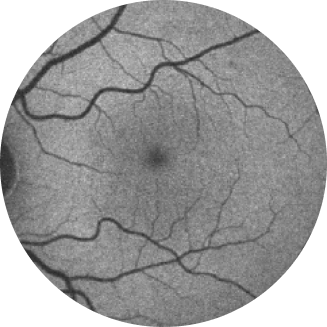

Retinografia de um olho saudável

Autofluorescência de fundo de olho normal de uma retina

A angiografia por autofluorescência do fundo ocular é, atualmente, uma tecnologia de imagem padrão para visualizar o epitélio pigmentar da retina (EPR) na atrofia geográfica.16